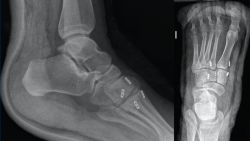

Figura 1. Caso 1. A: radiografía anteroposterior (AP) sin carga; B: radiografía oblicua sin carga; C: radiografía AP con carga con diástasis en la articulación de Lisfranc; D: radiografía lateral con carga.

Se trata de un varón de 32 años diagnosticado de lesión sutil de Lisfranc en urgencias tras un traumatismo deportivo sin especificar el mecanismo. Se realiza estudio radiográfico y tomográfico objetivando diástasis de 2 mm articular en el pie derecho sin lesión ósea (Figuras 1A y 1B). Se decide realizar tratamiento conservador con férula y descarga. Se hace una revisión a las 2 semanas, manteniendo la diástasis previa, pero en la revisión a las 6 semanas se confirma diástasis de 5 mm en la radiografía en carga, por lo que se indica tratamiento quirúrgico (Figuras 1C y 1D).